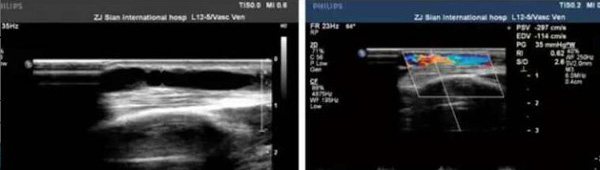

患者为通海县一名维持性血液透析患者,自体动静脉内瘘术后一年,近期透析时内瘘血管血流量明显不足(<200ml/min),故转诊我院肾内科。经CT血管造影术(CTA)检查发现左上肢动静脉内瘘血管头静脉段重度狭窄。术前经副主任孙阳及科室血管通路小组医护团队评估讨论,积极与B超室周宏伟主任沟通,于6月20日在B超引导下顺利进行了“内瘘血管狭窄球囊扩张成型术(PTA)”。该手术由周宏伟主任负责B超引导,肾内科卢永新主治医师负责操作,手术耗时一小时,内瘘血管狭窄段在球囊扩张下逐渐复张,术后B超评估显示狭窄段血管扩张良好,查体内瘘血管杂音及震颤明显增强,术后第二天使用内瘘血管行血透治疗,血流量达230ml/min以上,使用效果满意。

术后